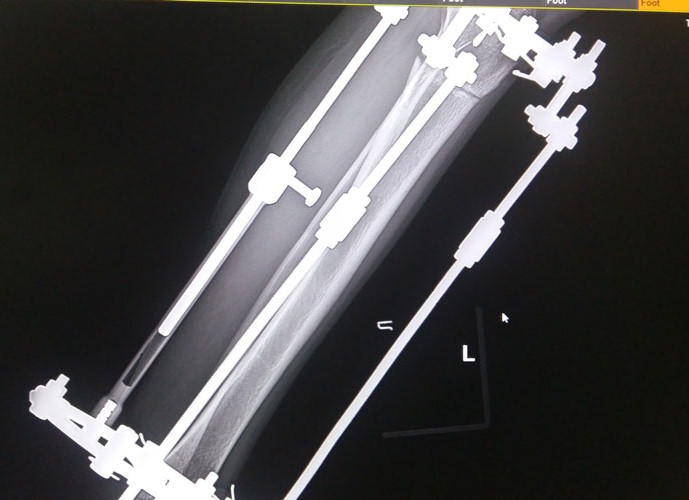

Рентген в 81 день с момента операции.

Здравствуйте, Соломея! По рентгену, у Вас всё отлично! В 90 дней возможно снятие аппаратов. Натаптывайте интенсивно ножки все эти дни, но без фанатизма(ведь когда я Вам говорю больше ходите- это значит, что при физ нагрузке быстрее разрастается костная ткань - вырабатывается, наступает сращение) лучше приехать и остаться у нас в клинике до снятия аппаратов. Один раз можно пожертвовать временем, расстоянием и средствами ради благополучия и отличного результата! Ножки мы исправляем один раз и навсегда!